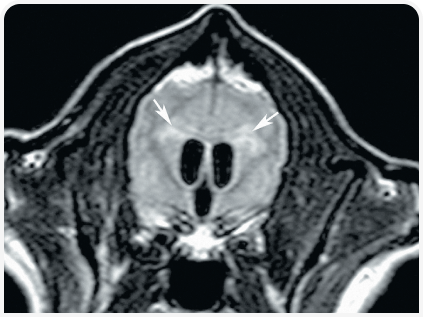

Диагноз ставится на основании изменения размера и формы черепа, неврологических признаков заболевания и нейровизуализации.